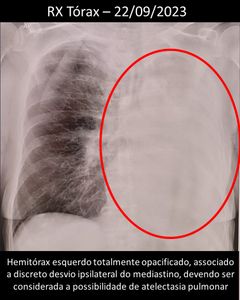

Em setembro, em questão de 6 meses, Dulce também emagreceu 15 kg, precisou ser internada novamente. Um novo raio x, apresentou o pulmão esquerdo agora todo tomado, e com isso a notícia de um desvio no esôfago, que literalmente, impedia ela de comer. Precisou começar sua alimentação por sonda nasoenteral na internação e na alta para casa, a notícia, de que de agora em diante, sua alimentação precisaria continuar pela sonda, em casa. A partir daí a família ja estava exausta fisica e emocionalmente e começou procurar cuidadoras para ajudar, pois dona Dulce precisa de atenção 24h por dia.